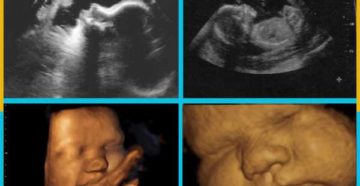

12 неделя беременности 12 неделя беременности по, так называемому, акушерскому календарю, которым привыкли руководствоваться медики,…

Как развивается плод на 10 недели беременности › Зачатие › Ожидание чуда меняет женщину, открывая…